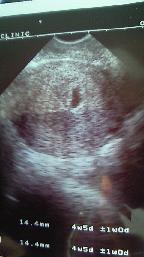

2008年3月17日

★2回目の検査★

女医さんがやっている病院が良かったので、探したらウチから車で10分くらいのところにあったので受診。

しかしここもお産はやっていなかった。

エコーの検査では1.4センチの胎嚢が写った。

もらった写真にパパも大感激。子宮外妊娠を心配していたのでとても安心した。

心音はまだ未確認。

【検診費用 4000円】